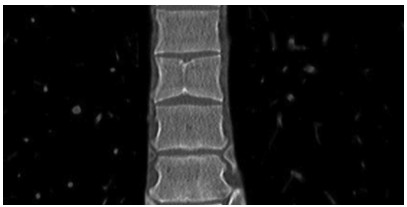

2型糖尿病合并糖原性肝病1例报告

2021, 37(9): 2183-2184. DOI: 10.3969/j.issn.1001-5256.2021.09.035

摘要(703) HTML (445) PDF (3125KB)(56)

摘要: